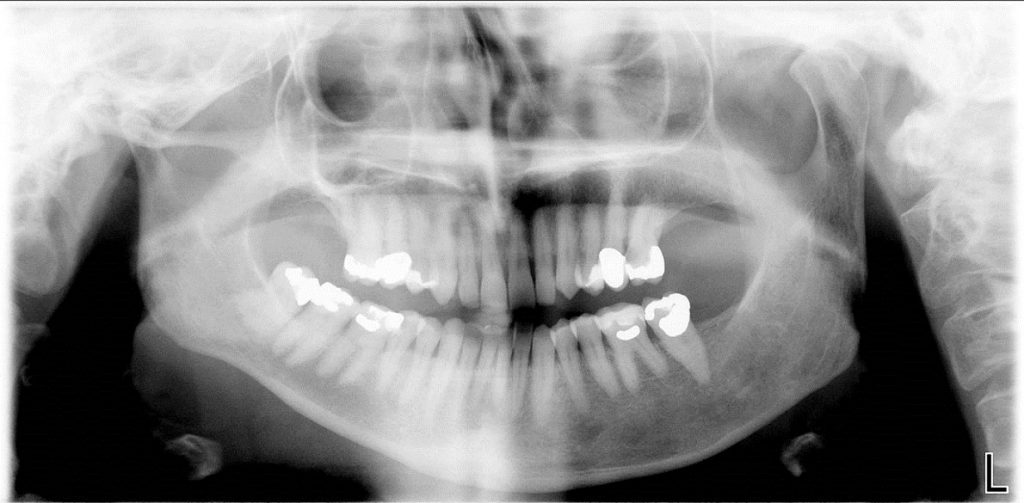

- Condylar Hypoplasia

- Hypoplastic condyle generally has normal shape and diminished size.

- Condylar neck is thinner and shorter.

- Joint space may be increased.

- Ramus and mandibular body may be hypoplastic resulting to facial asymmetry, hemifacial microsomia, mandibular retrognathism and malocclusion.